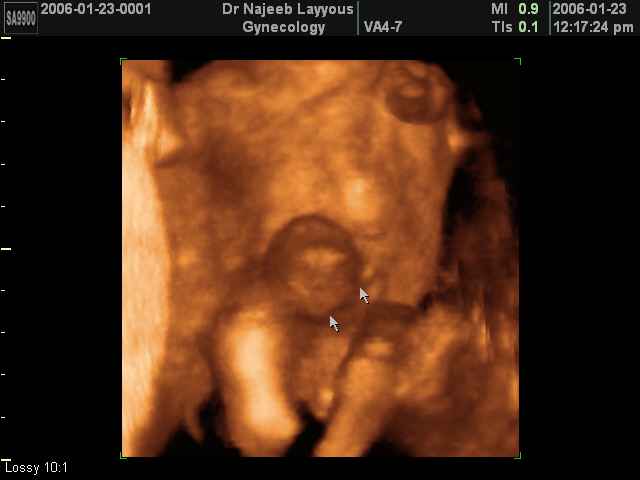

صور طبية للحمل بجهاز الالتراساوند | الدكتور نجيب ليوس